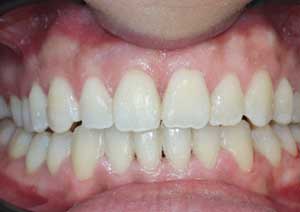

Traitement : Une ingression des molaires maxillaires avec une égression contrôlée du secteur antérieur a été réalisée à l’aide des arcs dits “Rocking Chair”, associés à des élastiques antérieurs portés de canine à canine, à droite et à gauche.

Cette mécanique permet de corriger la béance antérieure tout en conservant un contrôle précis de la position des dents antérieures et postérieures.

Après